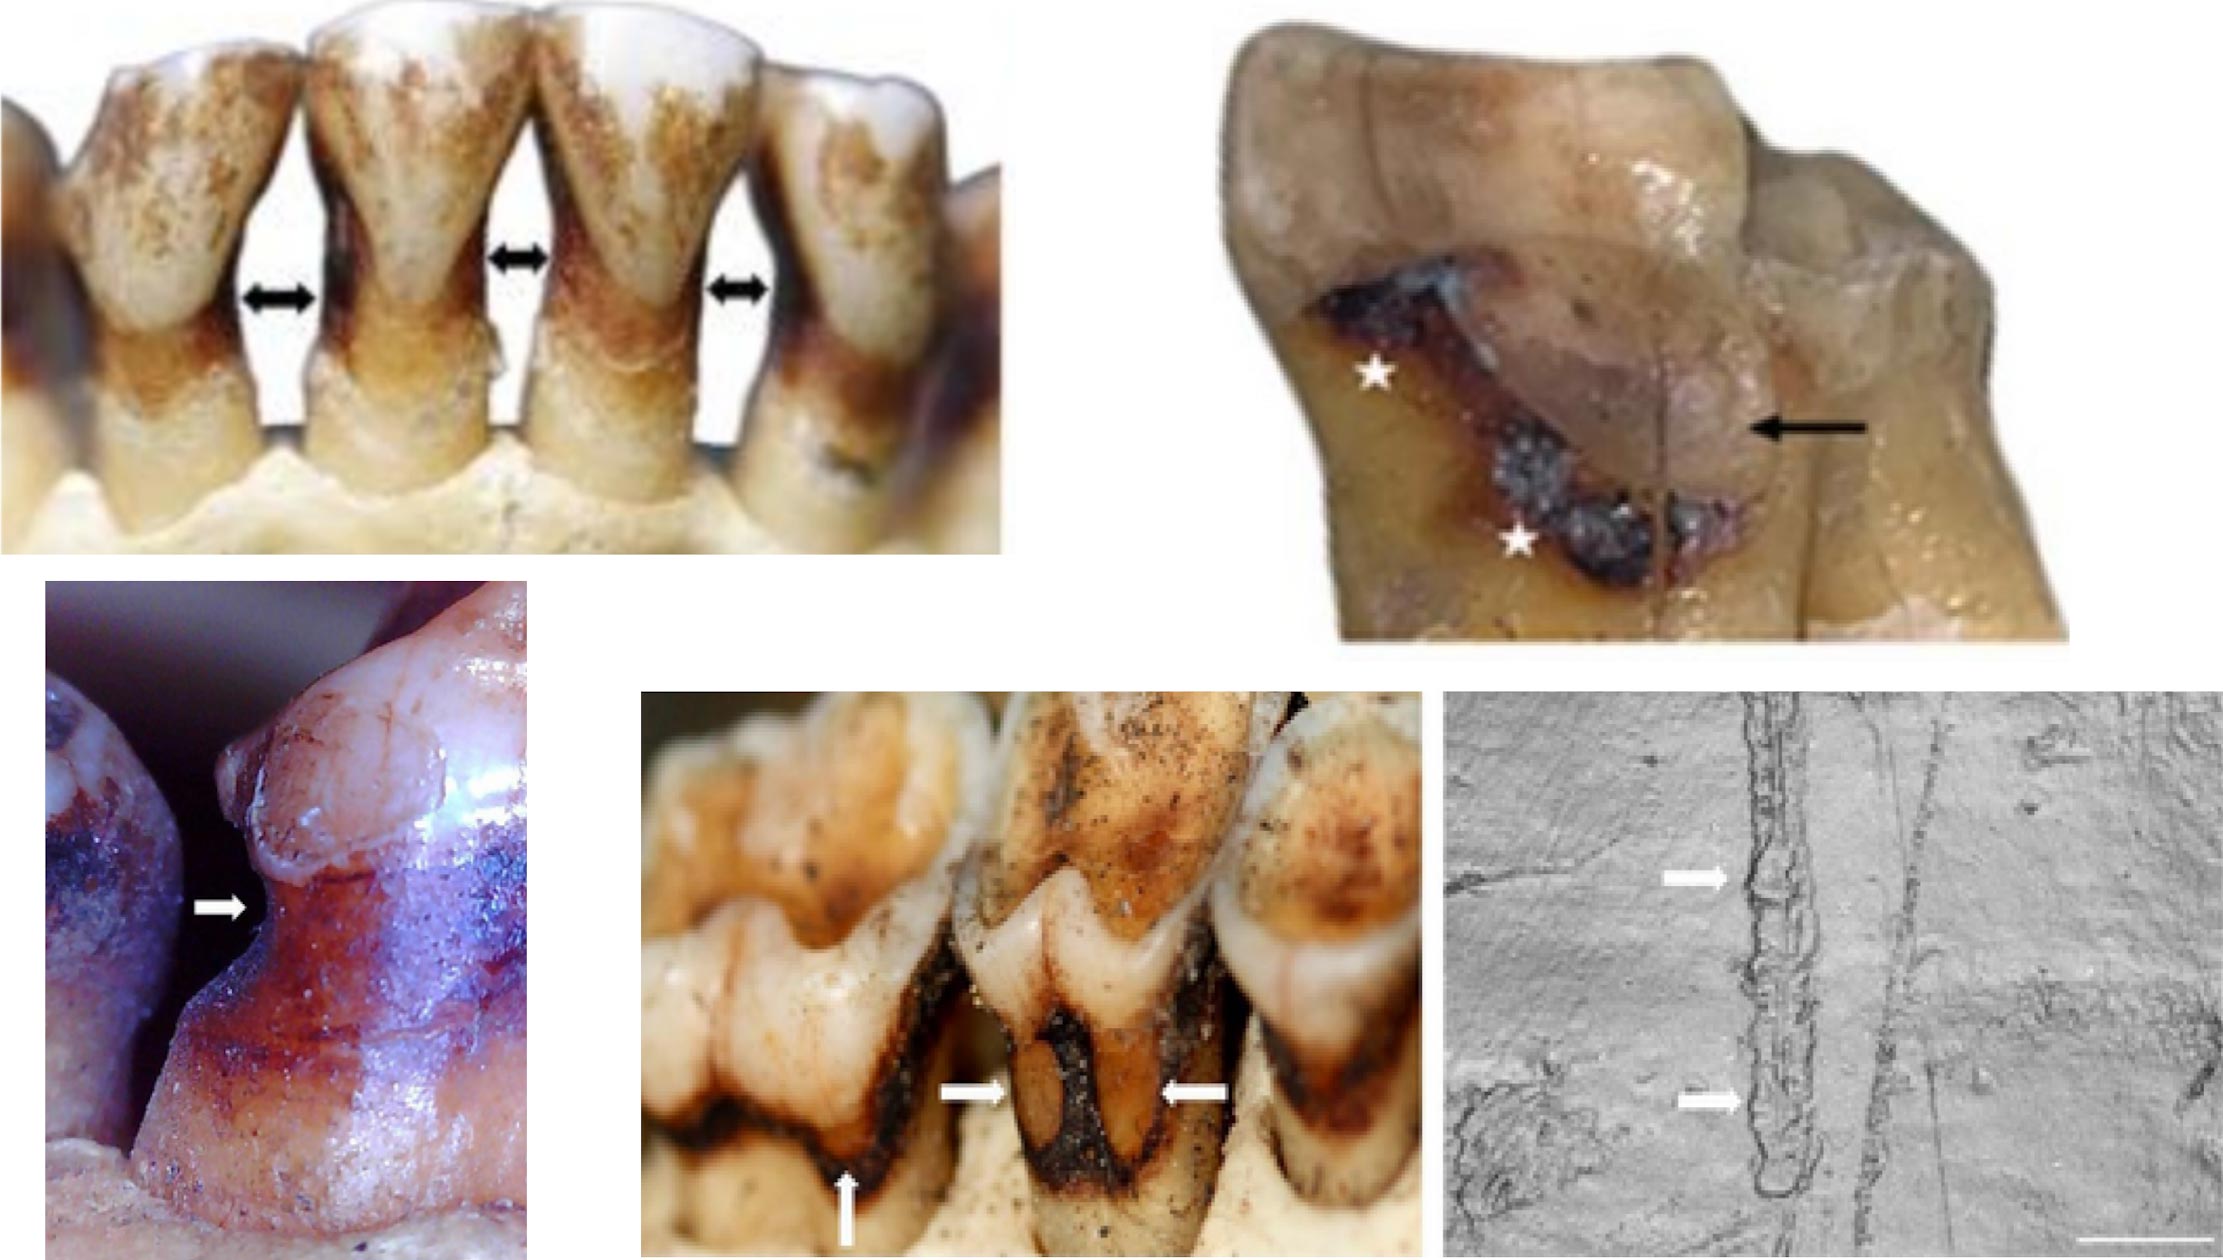

When researchers examined wild primate teeth — gorillas, orangutans, macaques, fossil apes — they found similar grooves in about 4% of individuals. Some looked almost identical to the human "toothpick" marks, complete with fine parallel scratches. Others were shallower and smoother, likely from acidic fruits that primates eat in large amounts. The point: these grooves weren't unique to humans, and they didn't necessarily mean tool use. Natural chewing, abrasive foods, even swallowed grit could produce the same pattern.

For more than a century, anthropologists spotted thin grooves running across the roots of fossil human teeth — especially between teeth. They labeled them "toothpick grooves" and interpreted them as evidence of tool use or deliberate dental hygiene. The marks appeared consistently across 2 million years of human evolution, from ancient hominins through Neanderthals. It seemed like a clear window into our ancestors' behavior.